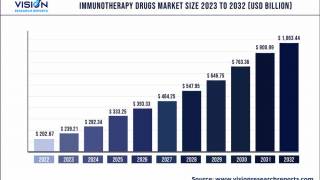

The research team will now look at different ways of improving the regime – including increasing the number of vaccinations or combining the vaccine with other therapies such as immunotherapies.